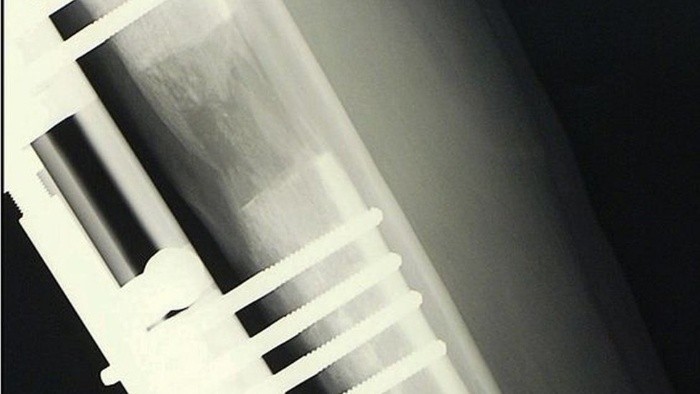

Según explicaron varios cirujanos consultados a BBC Mundo, el tratamiento estándar es el siguiente: primero se perfora y realiza un agujero en los huesos de las piernas, que luego se parten en dos.

Tras esto, se coloca quirúrgicamente una barra de metal en el interior del hueso y se mantiene en su lugar mediante una serie de tornillos.

Luego, la barra se va alargando lentamente hasta 1 milímetro cada día, extendiéndose hasta que el paciente alcanza la altura deseada y sus huesos se dejan hasta que sanen nuevamente.

El alargamiento de piernas es una operación compleja que implica muchos meses de recuperación. LIMBPLASTX INSTITUTE

El hueso, una vez separado, comienza a rellenar el espacio. GETTY IMAGES